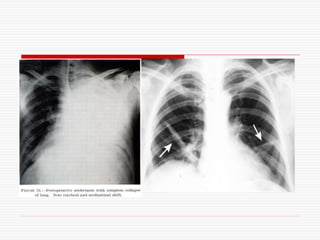

Lung and Pleural reflections:

Diagramatic representation of abnormal breath sounds